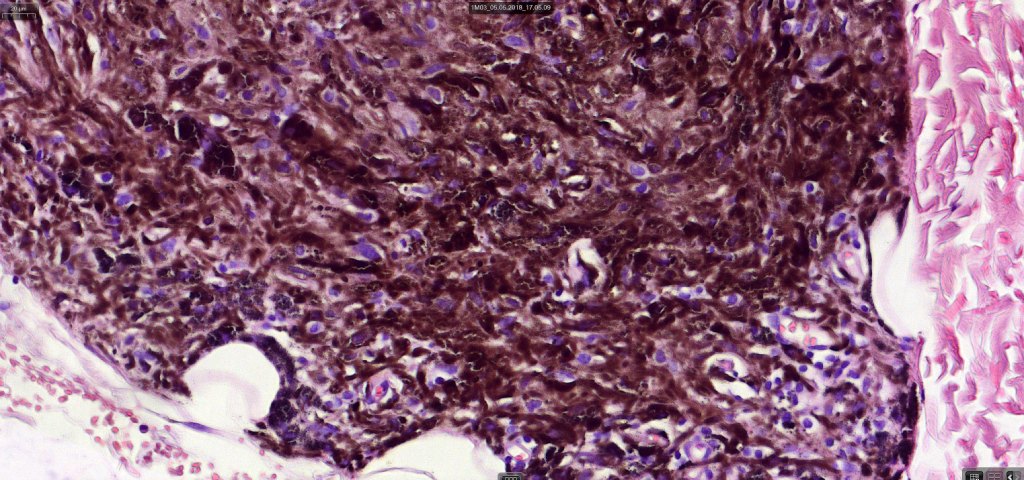

Histologically, it is characterized by a dense population of spindled, dendritic melnanocytes & melanophages with variable fibrosis. It may sometimes represent a component of a combined nevus. Mitotic activity is not usually present and pleomorphism is absent (see atypical blue nevus below). Involvement of the arrector pili muscle is not uncommon.

Very exceptionally, blue nevus also involves the epidermis (compound blue nevus).